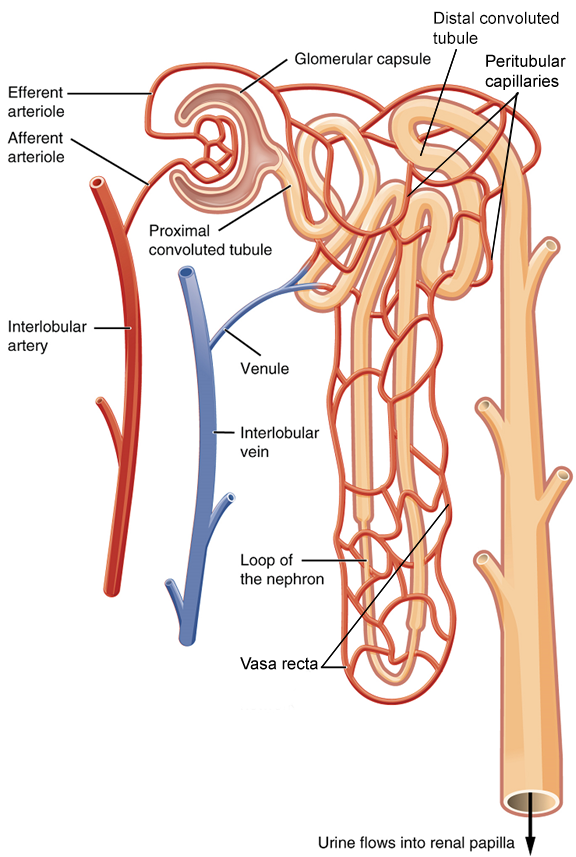

Nephrons and Vessels

The renal artery first divides into segmental arteries, followed by further branching to form interlobular arteries that pass through the renal columns to reach the cortex (Figure 3). The interlobar arteries, in turn, branch into arcuate arteries, cortical radiate arteries, and then into afferent arterioles. The afferent arterioles supply blood to about 1.3 million nephrons in each kidney.

Nephrons are the functional unit of the kidney; they take a simple filtrate of the blood and modify it into urine. They cleanse the blood and maintain the levels of blood chemical components within physiological values. The afferent arterioles form a tuft of high-pressure capillaries, the glomerulus. The rest of the nephron consists of a continuous tubule, the proximal end of which surrounds the glomerulus—this is Bowman’s capsule or glomerular capsule. As mentioned earlier, these glomerular capillaries filter the blood based on particle size.

The glomerulus and Bowman’s capsule together form the renal corpuscle. After passing through the renal corpuscle, the capillaries form a second arteriole, the efferent arteriole (Figure 7). These will next form a capillary network around the more distal portions of the nephron tubule, the peritubular capillaries and vasa recta, before returning to the venous system. As the glomerular filtrate progresses through the nephron, these capillary networks regain most of the solutes and water and return them to the circulation.

The glomerulus is a high-pressure capillary bed between afferent and efferent arterioles. Bowman’s capsule surrounds the glomerulus to form a lumen, and captures and directs this filtrate to the proximal convoluted tubule. As blood passes through the glomerulus, 10 to 20 percent of the fluid that moves into the glomerulus is captured by Bowman’s capsule and funneled to the proximal convoluted tubule.